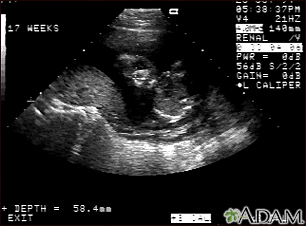

Ultrasound, normal fetus - face